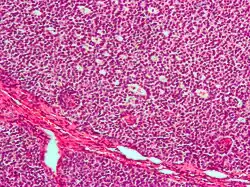

| Micrograph of a granulosa cell tumour, a type of sex-cord–gonadal stromal tumour. H&E stain. | |